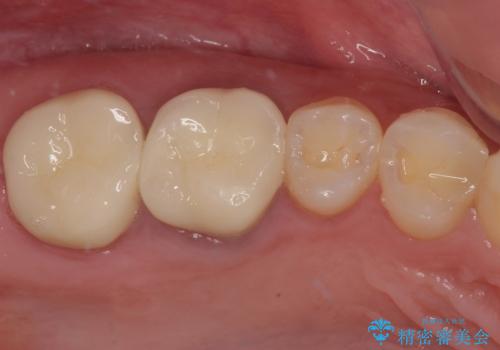

スペースが整った段階で、右下の第一大臼歯と第二大臼歯にインプラントを埋入。

その後、挺出していた右上第一大臼歯と第二大臼歯に装着されていた銀歯についても、審美性と適合性の向上を目的に、オールセラミッククラウンにやり替えました。

これにより、より自然で美しい見た目と、高い精度の咬合が得られています。